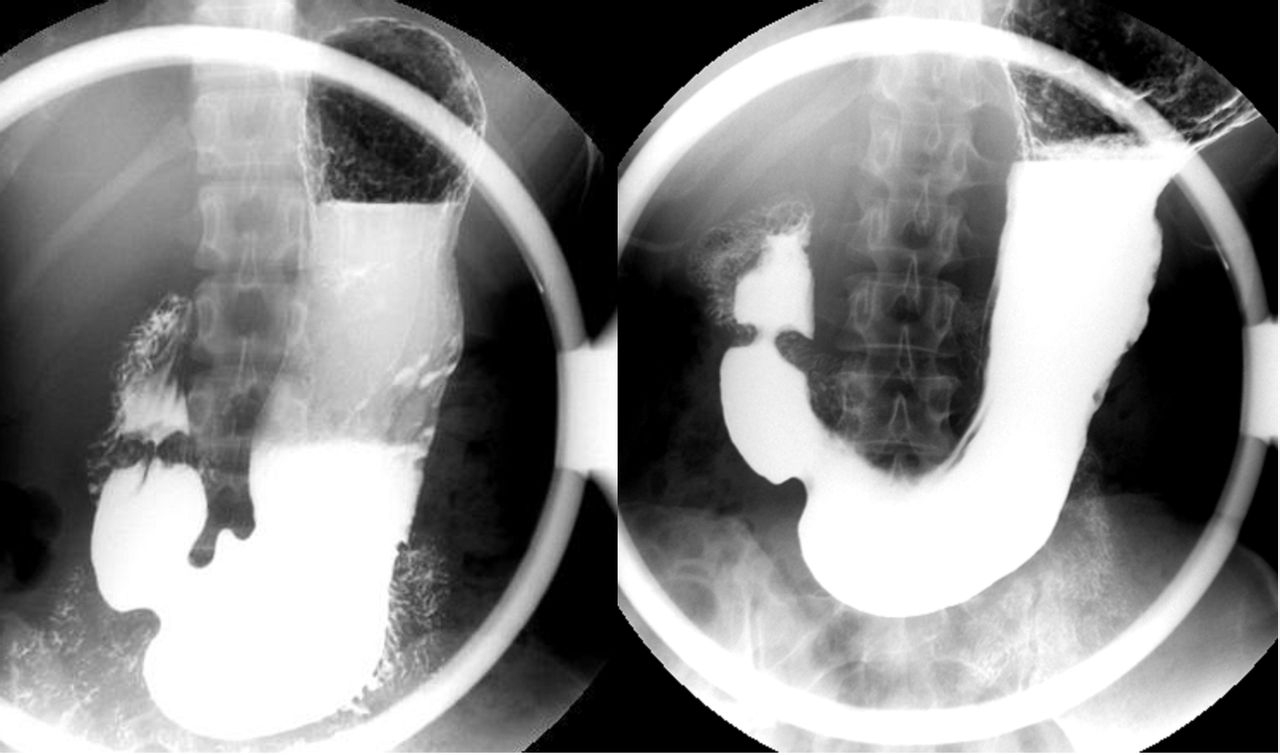

胃钡餐造影看息肉